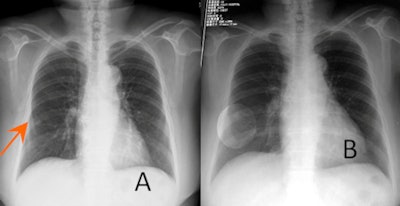

| CAD helps define the region of interest (ROI) harboring a subtle pulmonary nodule in a 79-year-old woman. (A) Arrow denotes nodule on x-ray. (B) CAD defines ROI. (C) CT indicates a small nodule in the middle lobe of the right lung. (D) A slide of sampled tissue from the nodule confirmed the presence of a well-differentiated adenocarcinoma. All images courtesy of Yan Xu, PhD. |